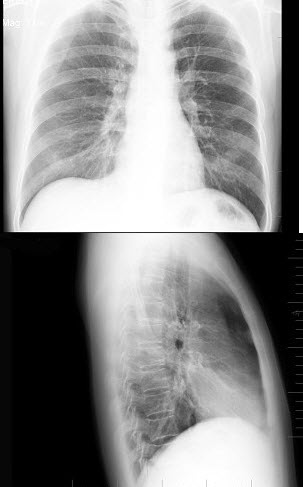

6、单项选择题

男,5岁,临床考虑先心病室间隔缺损,结合图像,下列描述正确的是()

A.肺淤血

B.正常肺

C.肺泡性肺水肿

D.间质性肺水肿

E.肺充血